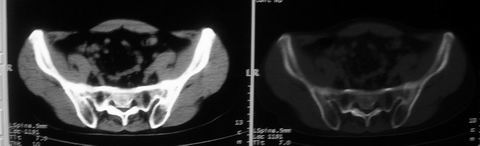

以下是引用余辉在2008-10-23 16:14:00的发言:[br]腰椎体棱角分明,小关节退变部分隔合,骶髂关节部分融合,考强脊炎